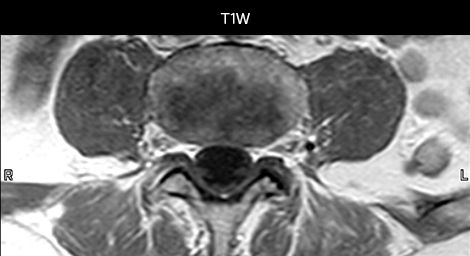

To minimize the time taken to perform scans, rapid MRI examination protocols (ExamCards) were developed, shortening the total scanning time to even less than 10 minutes in some exams. Techniques like mDIXON (modified DIXON) are used for robust capturing of fat-free MRI images in a hectic ED environment.